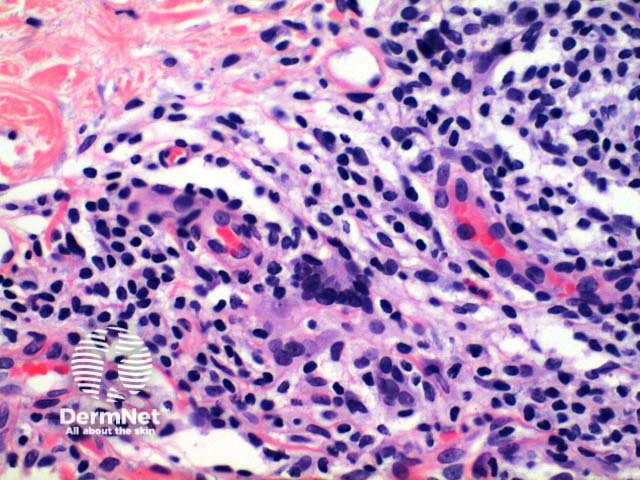

Scanning power view of lichen nitidus identifies a focal dermal inflammatory infiltrate enclosed within collarettes of epidermal acanthosis (Figures 1 and 2). Focal erosion of the epidermis in figure 1 indicates excoriation. Higher power view identifies a well circumscribed lymphohistiocytic infiltrate with multinucleated giant cells (Figures 3 and 4).